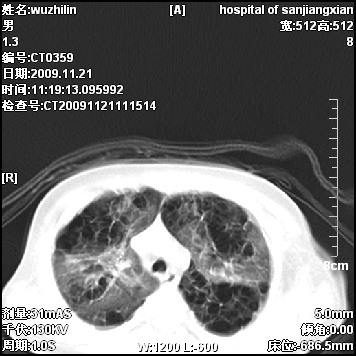

标题: PED3072: 1岁3个月患儿 胸部弥漫性病变 [打印本页]

标题: PED3072: 1岁3个月患儿 胸部弥漫性病变

弥漫性薄壁囊腔,胸膜下及肺底部占优势,双上肺磨玻璃密度影,首先考虑特发性肺间质纤维化,其次囊性肺纤维化,肺淋巴管平滑肌瘤病嗜酸性肉芽肿等;要结合临床综合考虑。

两肺布满多个薄壁含气囊腔,以下肺居多,伴磨玻璃样密度影,左侧气胸。两肺发育不全、两肺多发肺囊肿并感染,其次考虑肺囊腺瘤。